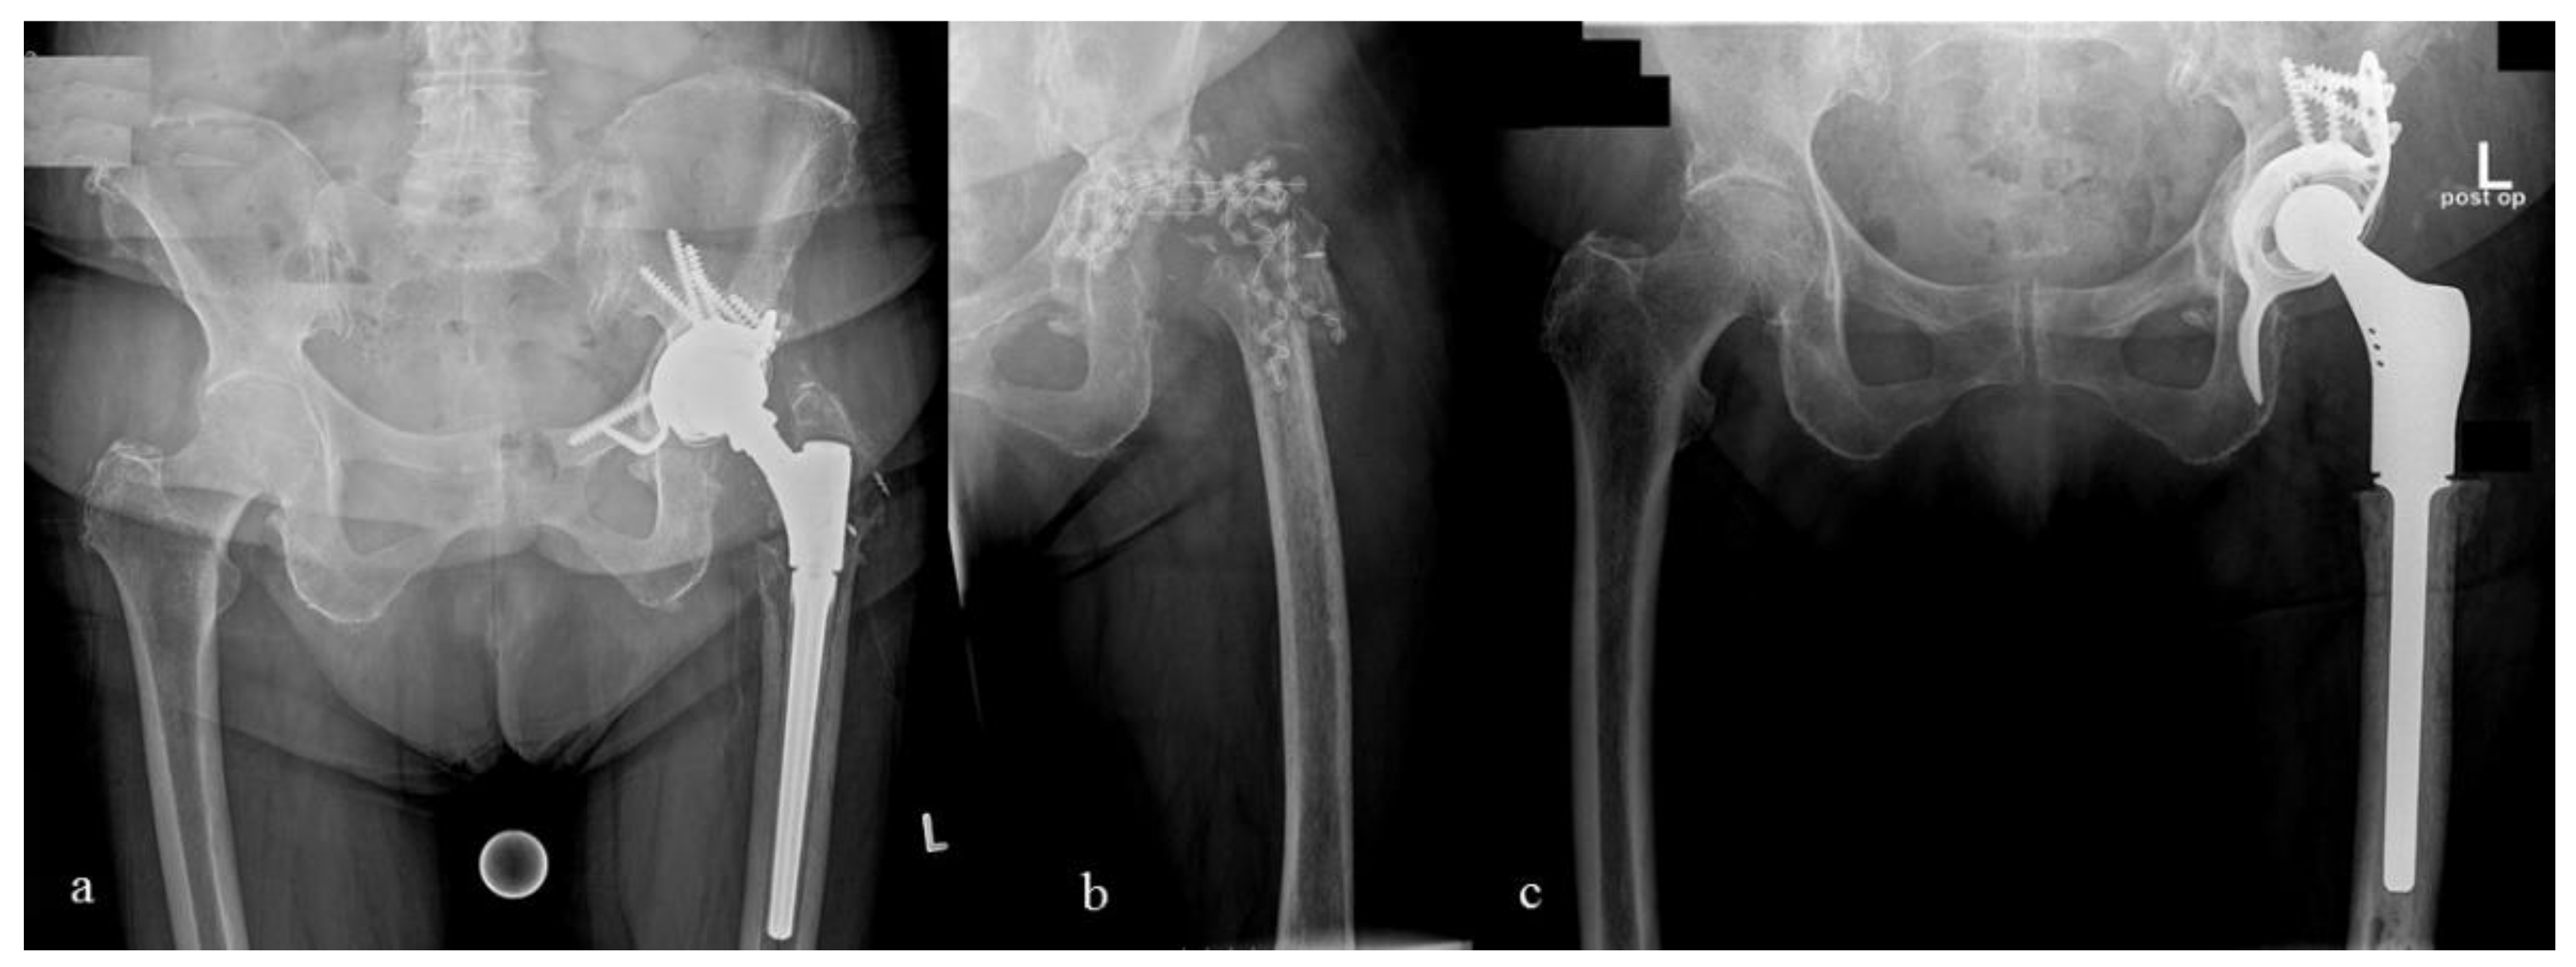

Postoperative AP hip radiograph after placement of antibiotic spacer Antibiotic Coverage After Hip Replacement There is scant evidence to support the use of periprocedural prophylactic antibiotics in the prevention of late total joint infection. You should receive antibiotic prophylaxis before any and all dental procedures that involve bleeding, including routine. The duration of antibiotic therapy in patients with prosthetic joint infection is primarily based on expert recommendations rather than. Postoperative antibiotic prophylaxis is currently. Antibiotic Coverage After Hip Replacement.